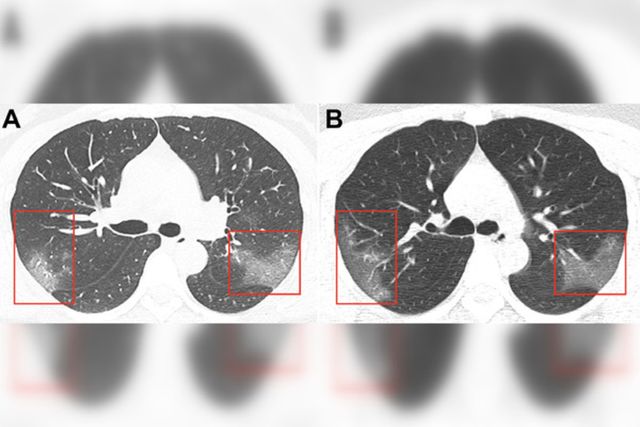

Лікарі заявили, що коронавірус може завдати серйозної шкоди легеням, а процес реабілітації може затягнутися на півтора-два роки.

"Після перенесеної коронавірусної інфекції в легенях спостерігаються фіброзні зміни, як після інших запальних захворювань легенів. Це буває після важкої пневмонії, при інтерстиціальних захворюваннях легенів. У людей йдуть структурні зміни, які вимагають тривалого відновлення", – зазначили фахівці.

При цьому, стверджують лікарі, прискорити процес одужання може дихальна гімнастика і зміцнювальний режим. Вони не протипоказані і їх можна проводити, але все буде залежати від індивідуальної здатності кожної людини, яка перехворіла на Covid-19, до структурного відновлення пошкодженого органу. Як це покращувати? Це тільки саме з часом може трапитися. Після перенесеного свинячого грипу N1H1 спостерігалися фіброзні ураження, які тривали протягом півтора-двох років. У декого легені не відновилися й досі.